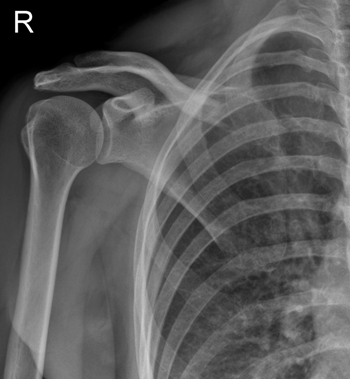

Неврологом было рекомендовано проведение Rg правого плечевого сустава для исключения патологии сустава (артроз?).

На Rg определяется остеолизис (на протяжении ~ 5 см) грудинного конца правой ключицы, край кости имеет неровные, нечеткие, зазубренные контуры. Также структура лопатки представляется резко разряженной.

При проведении КТ с контрастированием определяется остеолитическое поражение лопаток, ключиц, тел позвонков. Консультирован онкологами.

Диагноз: Множественная миеломная болезнь.